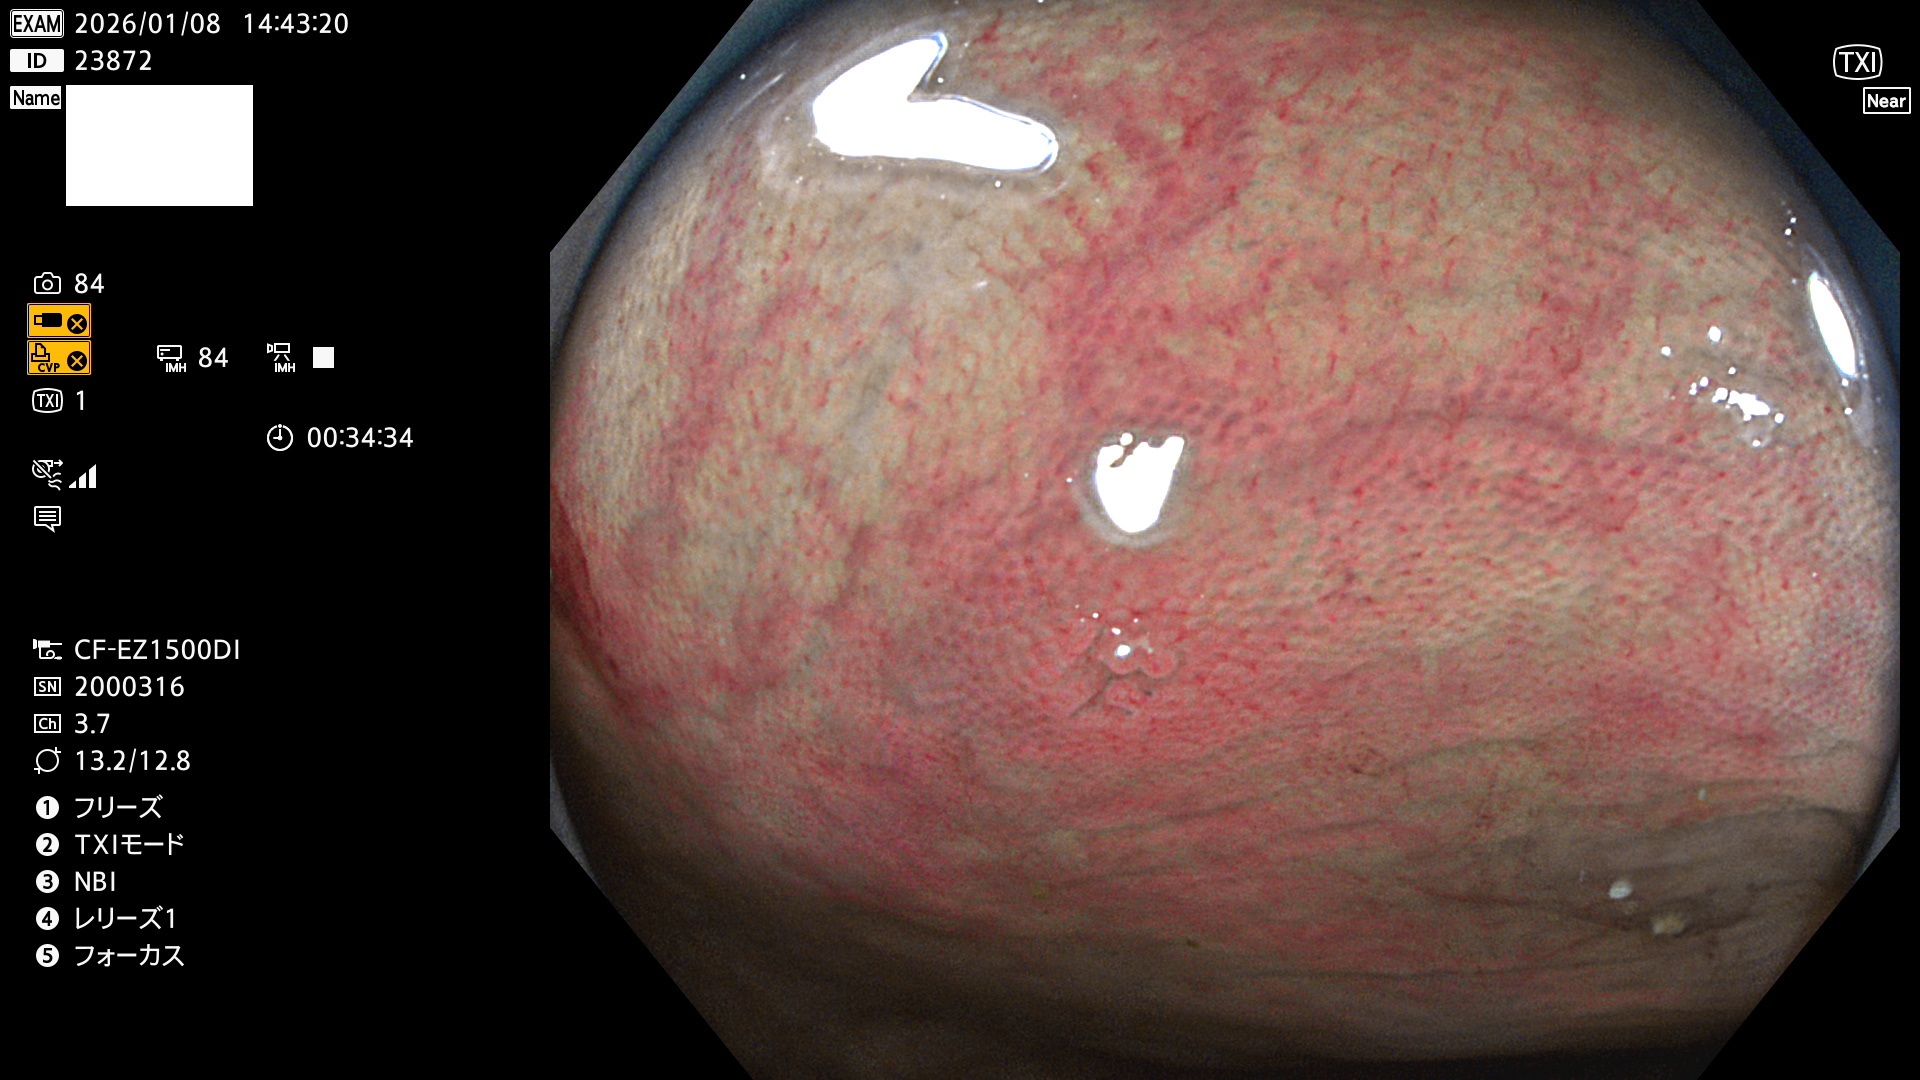

完全に平坦な物をUb、陥凹している物をUcと呼びます。Ubは認識が困難で、Ucはびらん(炎症)と紛らわしいために見落とされやすく、「内視鏡後・大腸癌」の原因になります。

専門的)Uc=De Novo癌? 内視鏡の解像度が低かった時代、このような説もありました。しかし今日の高精度内視鏡では良性の微小なUc型腺腫(APC遺伝子異常の腺腫)が日常的に見つかります。Ucこそが多段階発癌(Adenoma-Carcinoma Sequence)のMain Routeです。

毎週の検査(木・金・土・日)に発見されたUbとUc型・腺腫を、その週の日曜の夜にUPし1週間、提示します。

2026年1月8日〜1月11日の4日間(40件)6個 (Uc_ADR=6個/40人=15%)